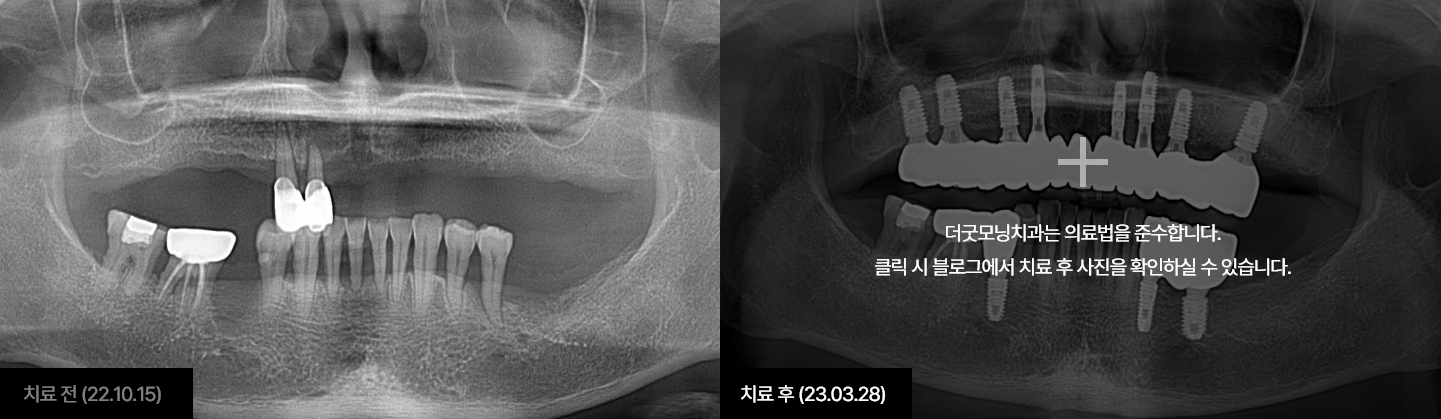

임플란트는 시술하는 의사의 수술 경험, 노하우에 따라 진료 결과가 달라지는

시술입니다.

잇몸뼈에 식립하여 자연치아를 대체해 주는 보철치료인 만큼

잇몸과

잇몸뼈에 대해 전문성이 높은 치주과 전문의가 진료해야 합니다.

더굿모닝치과는

보건복지부 인증 치주과+통합치의학과 더블보드 전문의가 직접 진료하며,

진단부터 식립, 최종 보철물까지 꼼꼼하게 완성해 드릴 것을

약속드립니다.

더굿모닝치과 블로그에서 해당 사례를 자세히 확인하실 수 있습니다.